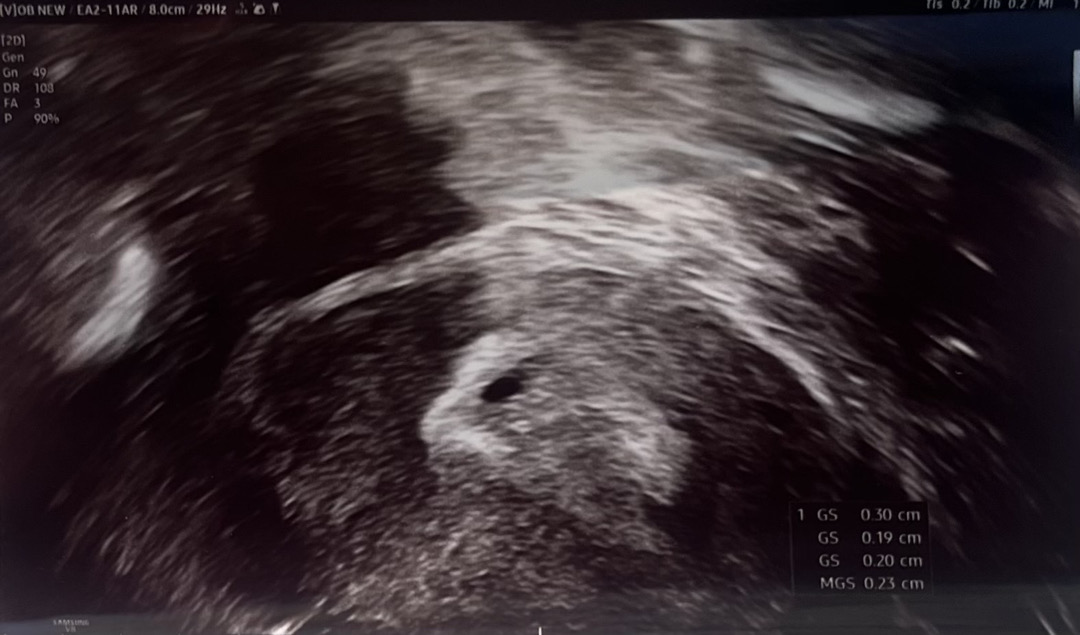

5주3일 아가집봤어요!

코딱쥐만한 집 봤어요ㅠㅠ 귀여웡,,, 2주 뒤에 심장소리 들으러 가용 히히